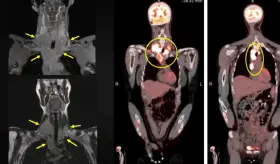

Meses después, desarrolló síntomas gastrointestinales y adenopatías torácicas que inicialmente hicieron sospechar una progresión metastásica, pero las biopsias revelaron granulomas no caseificantes sin células tumorales.

Este caso destaca la importancia de los estudios de imagen multimodales y plantea la necesidad de reconsiderar las estrategias de detección en mujeres no fumadoras, población en la que se observa un incremento creciente de esta neoplasia.